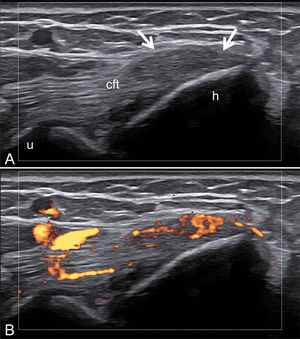

Furthermore, ultrasound reveals structural changes in the finger extensor tendons indicative of enthesitis, further demonstrating the utility of imaging in psoriatic arthritis evaluation (Fig. 8).

Fig. 8.Enthesitis at the Distal Insertion of the Extensor Tendon. Sonographic image obtained using Logiq e US system with an 8–18i MHz linear transducer. Comparative ultrasound images of the extensor tendon at the distal insertion in the same phalanx of both hands. One hand demonstrates significant thickening and hypoechogenicity indicative of enthesitis (B), while the other hand shows no such findings (A). Additionally, the presence of intra-tendinous power Doppler signal in the affected hand is noted as a sign of active enthesitis (C).